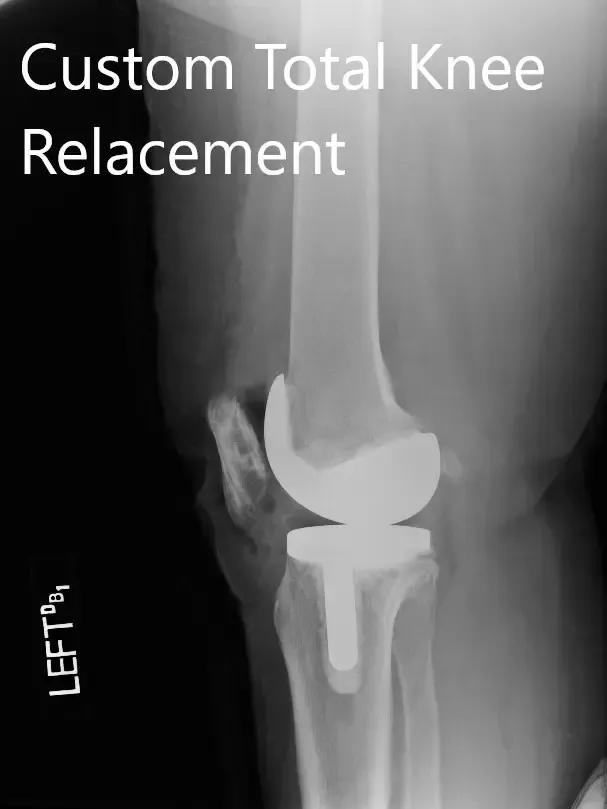

Postoperative X-ray images showing the AP and lateral views of the left knee